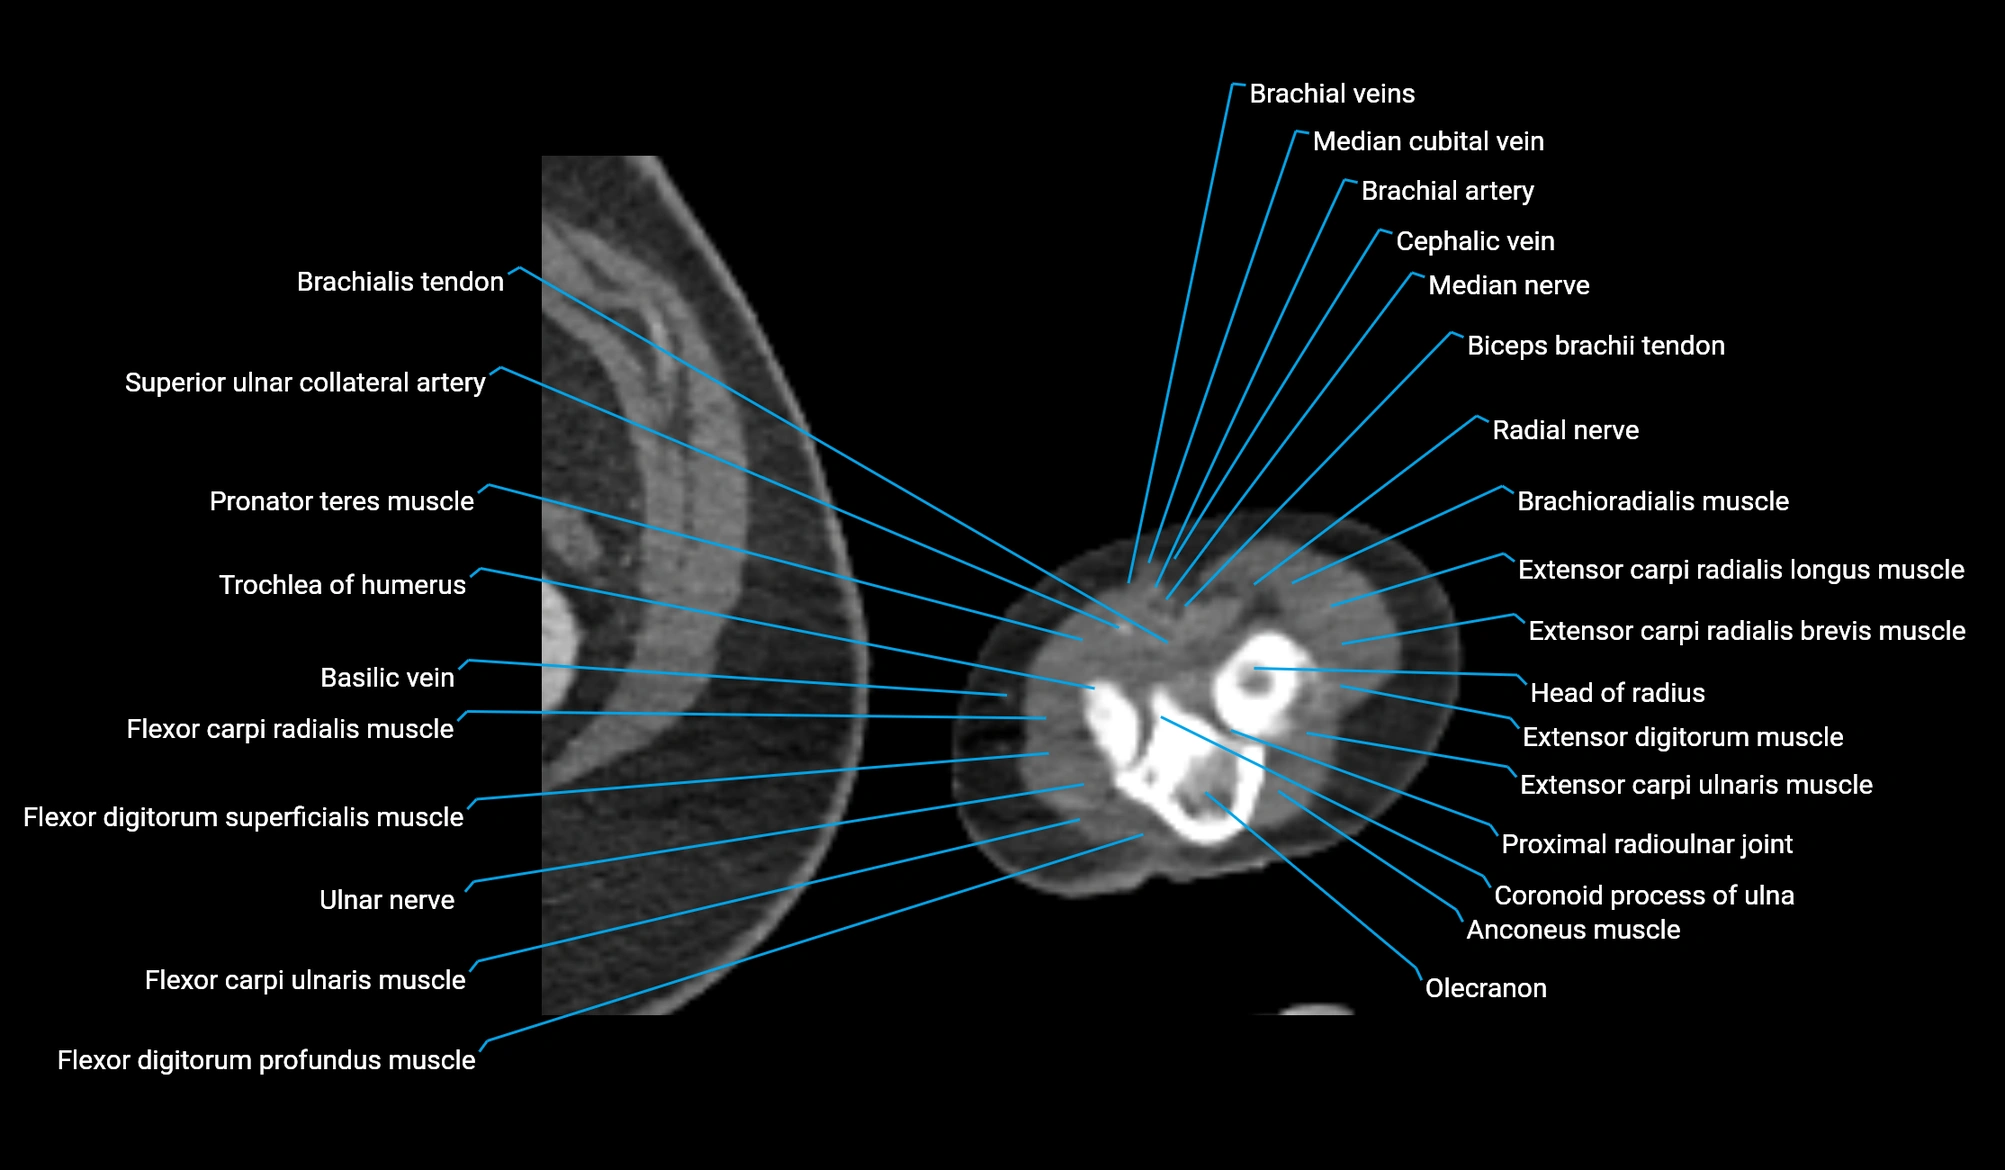

- Anconeus muscle

- Biceps brachii tendon (distal)

- Brachioradialis muscle

- Coronoid process of ulna

- Extensor carpi radialis brevis muscle

- Extensor carpi radialis longus muscle

- Extensor carpi ulnaris muscle

- Extensor digitorum muscle

- Flexor carpi radialis muscle

- Flexor carpi ulnaris muscle

- Flexor digitorum profundus muscle

- Flexor digitorum superficialis muscle

- Head of radius

- Median cubital vein

- Median nerve

- Olecranon

- Pronator teres muscle

- Proximal radioulnar joint

- Radial nerve

- Superior ulnar collateral artery

- Trochlea of humerus

- Ulnar nerve